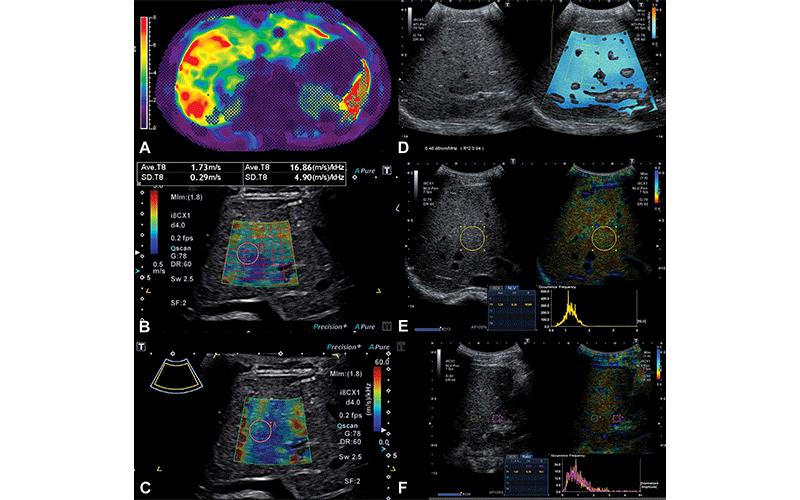

Representative MR elastography and quantitative US images in a 16-year-old boy with Fontan-associated liver disease and elevated liver shear stiffness (5.4 kPa with gradient-recalled echo MR elastography). (A) Axial MR elastogram with 95% confidence map overlay shows a stiff (5.4 kPa) heterogeneous liver. Image colors are indicative of stiffness (in kilopascals) according to the scale in the left of the elastogram image. (B) Transverse two-dimensional shear-wave elastography US image with shear-wave speed of 1.73 m/sec (9.0 kPa). (C) Transverse shear-wave dispersion map with dispersion of 16.86 m/sec/kHz. (D) Split-screen transverse image shows liver attenuation measurement of 0.46 dB/cm/MHz. (E) Split-screen transverse image shows normalized local variance measurement of 1.24. (F) Split-screen longitudinal image shows hepatorenal index measurement of 1.07. ATI-Pen = attenuation imaging penetration mode frequency, DR = dynamic range, fps = frames per second, G = gain, i8CX1 = Canon Apio i8CX1 transducer, Ml = mechanical index, NLV-Pen = normalized local variance penetration mode frequency, SF = spatial filter, Sw = shear-wave frequency. https://doi.org/10.1148/radiol.212995 ©RSNA 2022